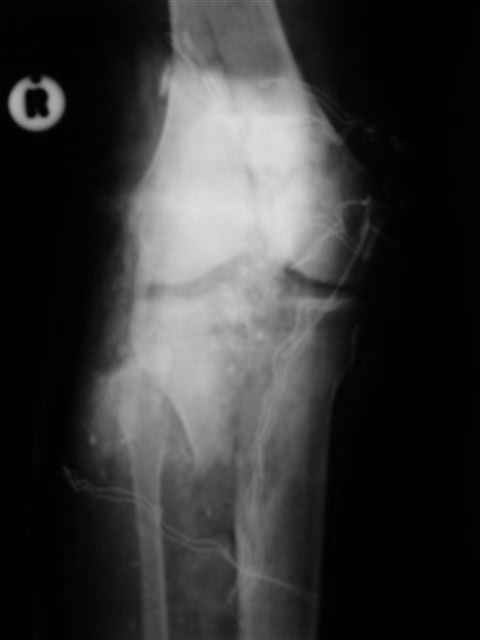

Спасибо за комментарии. Травма тяжелая с проблематичным прогнозом для функции коленного сустава( изначально травма разгибательного аппарата с последующим частичным некрозом собственной связки надколенника и о обнажением рефиксированного фрагмента бугристости большеберцовой кости, дефектом центрального отдела суставной поверхности большеберцовой кости и медиального отдела капсулы сустава).

№4 снимок через два дня после операции, супракондилярный перелом, при поступлении конечность была холодная и без пульса, подозрение на повреждение сосудов, сделана ABI (ankle-brachial index) в приемном отделении, индекс меньше 1 к 0.9 в норме 1 к 1.1, срочная ангиография в операционной после Ex-Fix, по два стержня в сегменте наложен в течение 20 мин, повреждение подколенной артерии, ушивание сосудистым хирургом через медиальный доступ в дистальном отделе бедра и двухразрезная профилактическая фацсиотомия, перкутанная фиксация каннюлированными шурупами несмещенного перелома шейки бедра и дополнительные стержни в фиксаторе для жесткости.